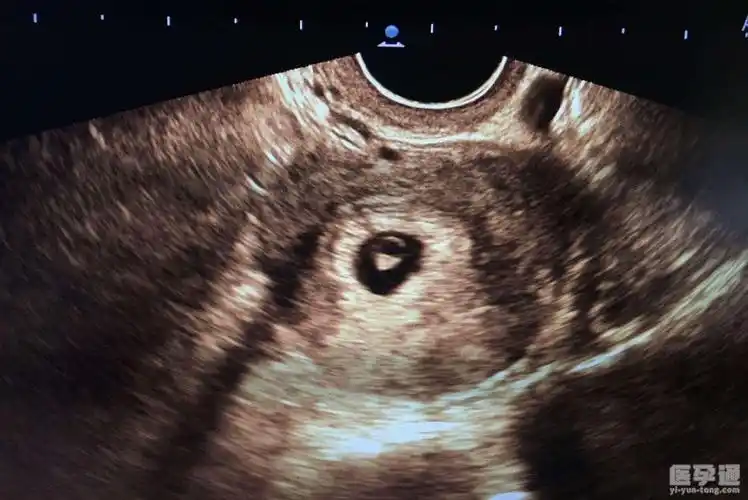

怀孕42天拍的,有谁会看男女吗?

42天孕囊男女到底怎样看更准总结三个方面90的妈妈们都说准

42天的孕囊图,会看的宝妈进来看看是男孩还是女孩